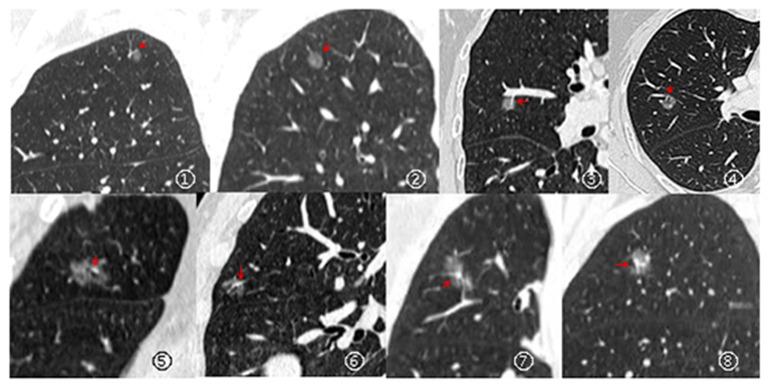

Overall, 506 patients with 561 GGNs on routine computed tomography images, obtained between January 2017 and March 2021, were enrolled in this single-center, retrospective Chinese study. Moreover, the cLung-RADS 1.1 was previously validated, and the DL algorithms were based on a multi-stage, three-dimensional DL-based convolutional neural network. Therefore, the DL-based cLung-RADS 1.1 model was created using a combination of the risk scores of DL and category of cLung-RADS 1.1. The recall rate, precision, accuracy, per-class F1 score, weighted average F1 score (F1), Matthews correlation coefficient (MCC), and area under the curve (AUC) were used to evaluate the performance of DL-based cLung-RADS 1.1.

本研究为单中心回顾性中国研究,共纳入 2017 年 1 月至 2021 年 3 月期间在常规计算机断层扫描图像上获得的 506 例 561 个 GGN 患者。此外,cLung-RADS 1.1 先前已得到验证,DL 算法基于多阶段三维深度学习卷积神经网络。因此,基于 DL 的 cLung-RADS 1.1 模型是通过结合 DL 的风险评分和 cLung-RADS 1.1 的类别创建的。使用召回率、精确度、准确度、每类 F1 分数、加权平均 F1 分数(F1)、马修斯相关系数(MCC)和曲线下面积(AUC)来评估基于 DL 的 cLung-RADS 1.1 的性能。